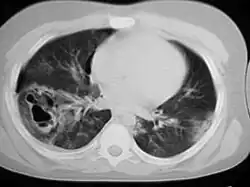

| A chest CT scan revealing pulmonary contusions, pneumothorax, and pseudocysts | |